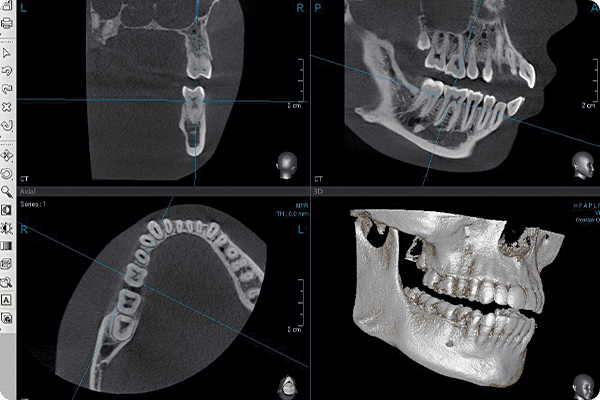

컴퓨터 분석 임플란트

(3D CT)환자의 잇몸뼈와 턱뼈 상태를 3차원 입체 영상으로

정밀하게 진단하여 수술 오차를 줄입니다. -

3D CT&디지털 치아 스캐너 정밀 진단3D CT와 치아 스캐너의 데이터를 결합하여, 임플란트를 실제로 심었을 때 가장 이상적인 위치에 식립될 수 있도록 지향합니다.

수술 가이드는 실질적으로 네비게이션

역할을 하는 장치로, 모의 수술 계획과

동일한 위치와 각도로 임플란트를

식립할 수 있게 됩니다.

미리 계획된

위치에 수술이 진행되기 때문에

수술 시간이 짧고

체력적으로도 부담이 적습니다.

치료기간이 오래 걸릴 것 같아요컴퓨터 분석 임플란트는 수술 전 3차원 CT촬영과

가상수술을 통해 미리 설계된 위치에 임플란트를

식립하기 때문에 수술시간이 단축될 뿐만 아니라

잇몸 절개 범위를 줄여

출혈과 붓기, 실밥으로 인한 불편함 등

수술 후 나타날 수 있는 합병증을 줄일 수 있습니다. -

임플란트 부작용이 걱정돼요CT 촬영을 토대로 제작된 3차원 입체영상을 통해

환자의 치아는 물론 신경구조물에 대한 정밀한 진단이 가능하고

가상수술로 임플란트 식립 할 위치를 파악할 수 있어

부작용 및 신경손상에 대한 우려를 줄일 수 있습니다. -